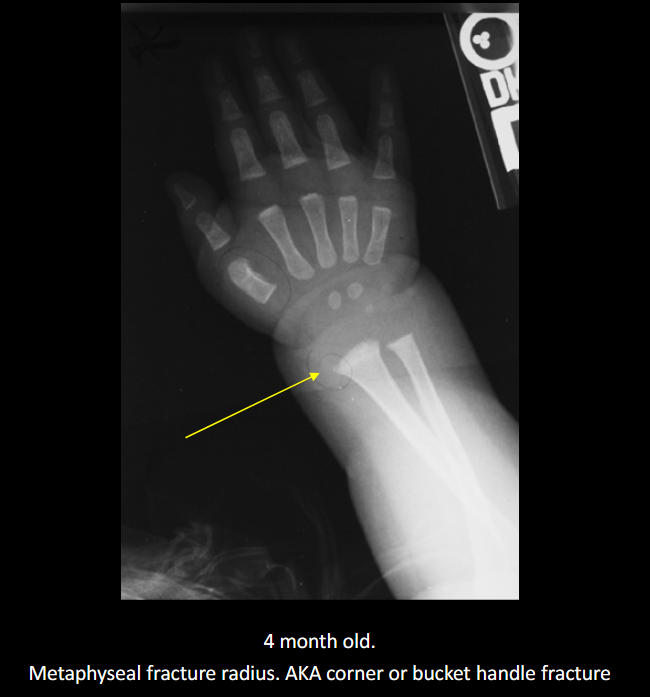

Define NAI.

Non-accidental injury/trauma; deliberate physical harm to a child.

Classic metaphyseal injury in NAI?

Corner/bucket-handle fracture.